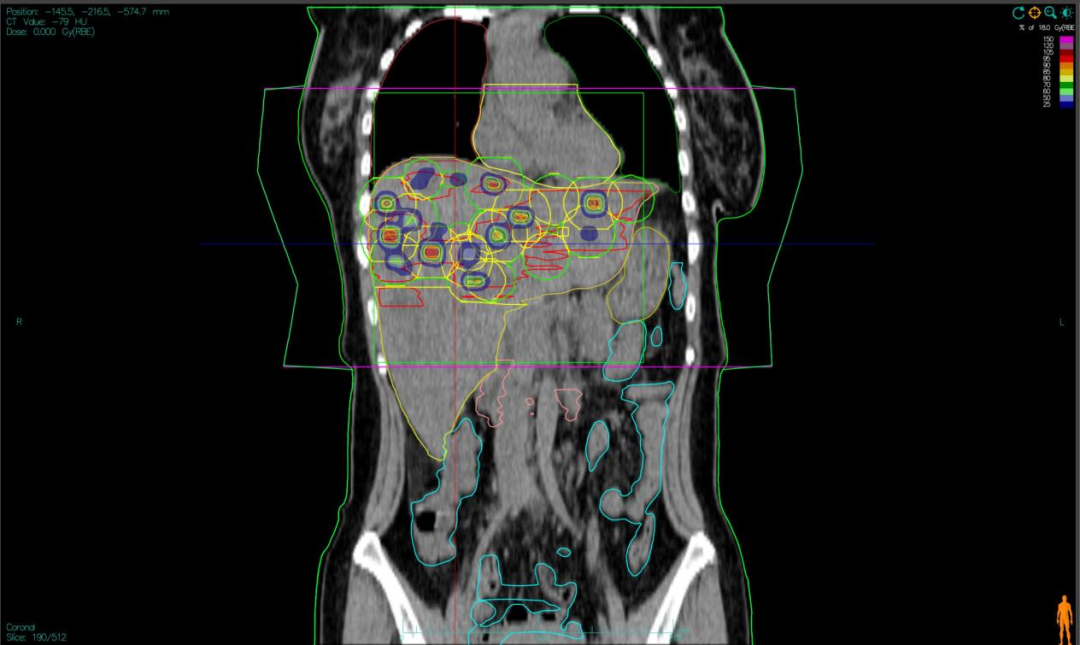

“双布拉格”,并非指代两个物理峰值,而是两大核心治疗理念的深度碰撞与融合。第一个“布拉格”,是物理学范畴的布拉格峰——重离子束流可在体内特定深度释放绝大部分能量,这一特性构筑起“指哪打哪”、极致保护正常组织的物理基石。第二个“布拉格”,是免疫学范畴的布拉格治疗,即国际前沿的PRaG协同治疗方案。它通过精准放疗在局部“点火”,释放肿瘤抗原;以GM-CSF为“导航”,引导免疫系统识别肿瘤细胞;再借助PD-1抑制剂“解除免疫刹车”,让免疫细胞能够持久、全身性地攻击肿瘤,最终追求珍贵的“远隔效应”。而晶格放疗,正是连接两大“布拉格”理念的关键桥梁。针对常规手段无法照射的巨大肿瘤,它将均匀剂量场转化为无数离散的高剂量“能量岛屿”。这种模式不仅能奇迹般保护穿插其中的正常组织与脉管结构,其独特的剂量分布,更被证实可高效诱发免疫原性细胞死亡,将物理打击的能量,转化为激活全身免疫反应的“信号”,让肿瘤的局部治疗与全身控制成为现实。

四大优势协同发力:一,依托重离子射线特有的“布拉格峰”物理特性,实现对深部肿瘤的“定点爆破”;二,采用“晶格放疗”先进布野技术,在巨大肝肿瘤内部精准布设能量“棋盘格”,在高效杀伤肿瘤细胞的同时,为残存正常肝组织与关键脉管留存生存空间;三,将此次精准物理打击,完美嵌入“布拉格治疗”免疫协同策略,以此作为激活全身免疫反应的“点火器”,联合PD-1抑制剂与GM-CSF,力求激发远隔效应,对未被照射的病灶形成攻击;四,引入干细胞支持下的新一代免疫细胞疗法,整合诱导多能干细胞(iPSCs)或间充质干细胞(MSCs)来源的免疫效应细胞(如CAR-T、CAR-NK和TCR-T细胞)与工程化技术,提升癌症免疫治疗的可及性与疗效。